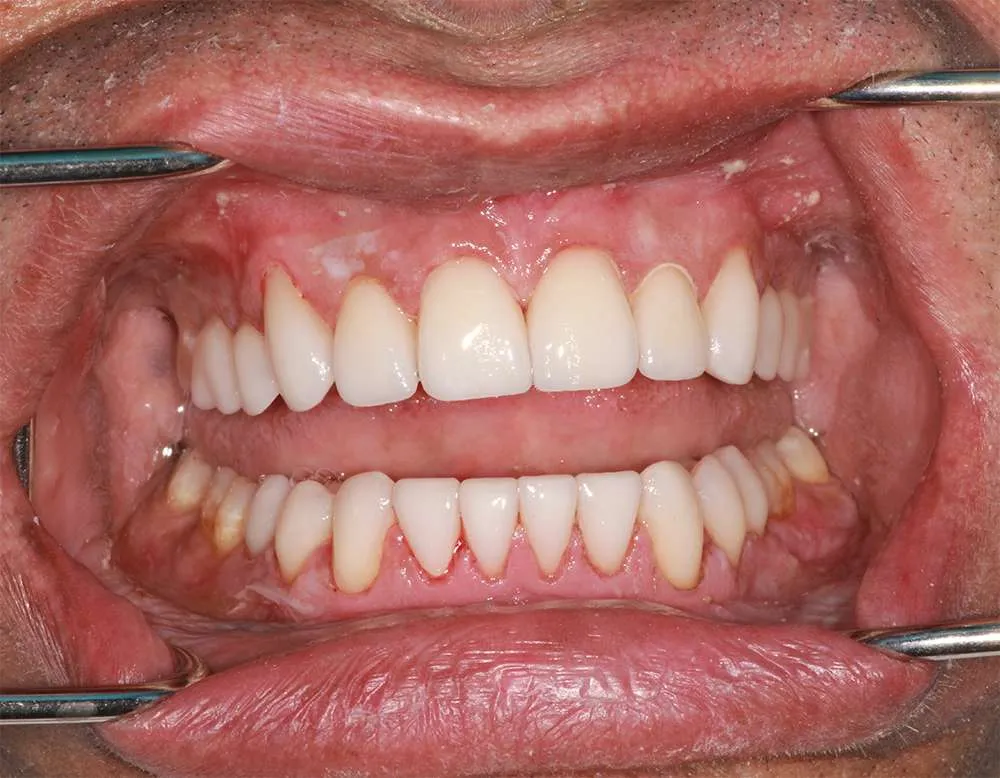

Real Stories, Real Results: Case Studies Showcasing How Our Personalized Approach Transforms Smiles and Lives

Complex Cases

Witness the Remarkable Changes We Can Achieve

One of the most significant benefits of ultra-thin veneers is that they require minimal removal of the tooth surface, allowing you to preserve your natural tooth structure. Traditional veneers often necessitate the removal of a substantial amount of enamel, which can weaken the teeth over time. In contrast, ultra-thin veneers are designed to be as thin as a contact lens, which means that only a small amount of your tooth surface needs to be etched. This preservation of your natural enamel results in a healthier, stronger tooth that maintains its integrity and function.

Ultra-thin veneers are crafted from high-quality materials that closely resemble the look and feel of natural teeth. The translucency and texture of these veneers mimic the appearance of real enamel, ensuring that your smile looks natural and aesthetically pleasing. Each veneer is custom-made to match the color, shape, and size of your existing teeth, blending seamlessly with your natural smile. This attention to detail ensures that your veneers are virtually indistinguishable from your natural teeth, providing you with a flawless, beautiful smile.